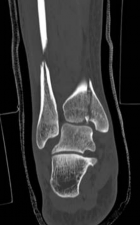

Standard orthogonal radiographs (anteroposterior and lateral) are sufficient for initial diagnosis, but they routinely underestimate the complexity of partial articular fractures. A high-resolution computed tomography (CT) scan with two-dimensional multiplanar reformats (coronal and sagittal) and three-dimensional surface rendering is considered the standard of care.

CT imaging is critical for:

1. Identifying the exact location and size of the articular fragments.

2. Detecting central articular depression that is obscured by the cortical rim on plain films.

3. Mapping fracture lines extending into the diaphysis.

4. Planning the surgical approach to ensure direct access to the primary fracture line.